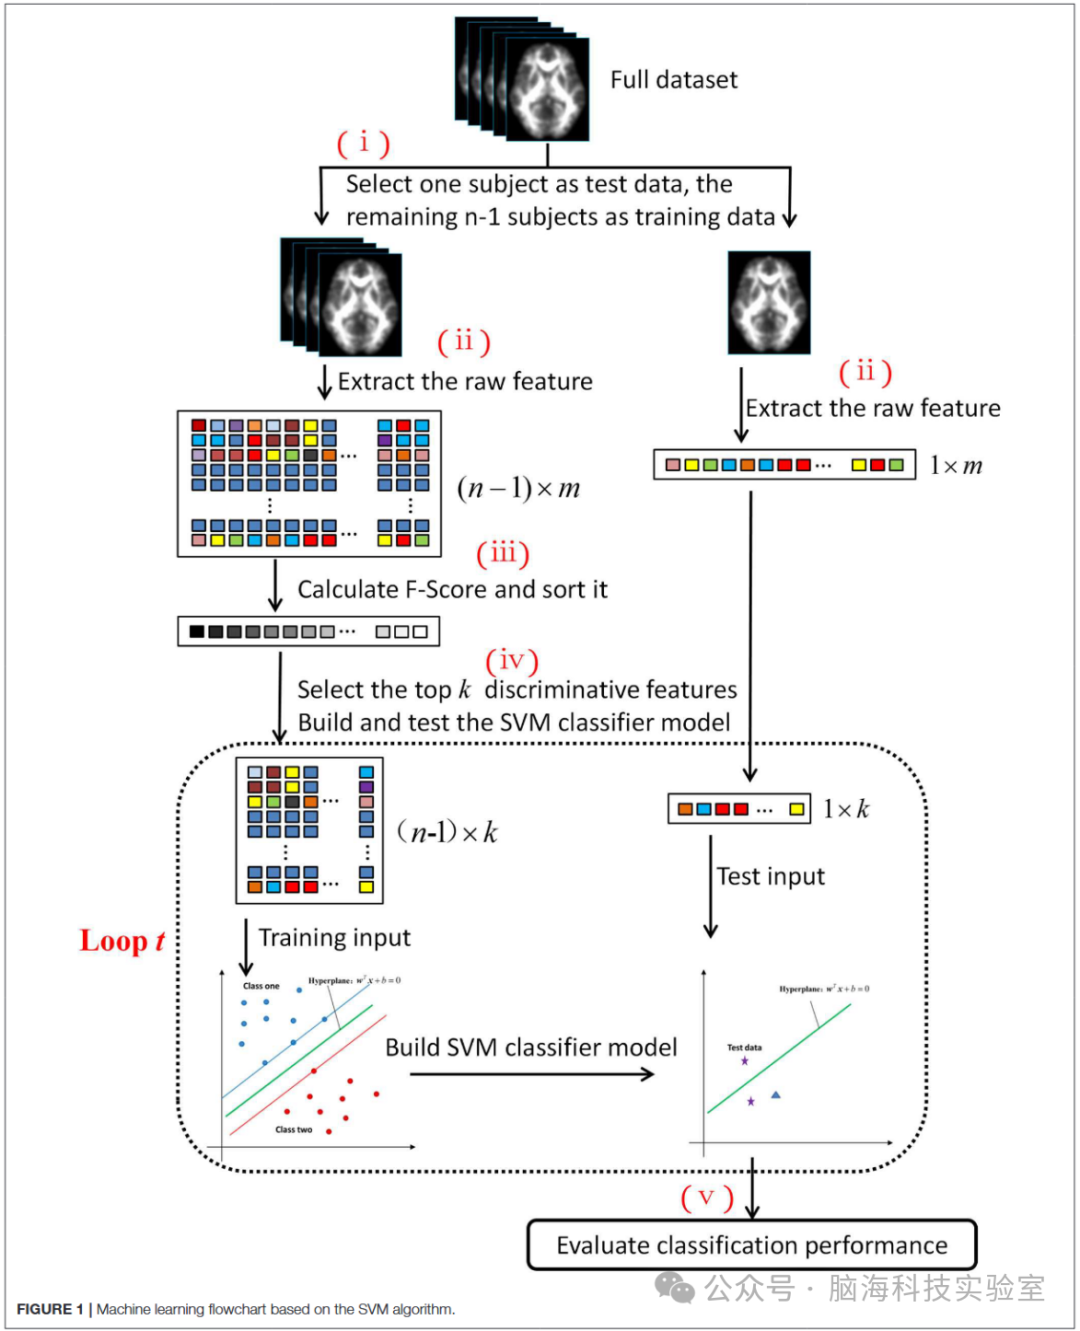

图1展示了机器学习过程的五个步骤:(i)将整个数据集分为两部分:一个受试者作为测试集,其余的组成训练集;(ii)从DTI图像中提取特征;(iii)计算每个特征的费舍尔分数并对特征进行排序;(iv)选择排名前k的判别特征来构建SVM分类器模型并对其进行测试;以及(v)评估机器学习分类的性能。代码基于LibSVM工具箱在MATLAB(2016a版,MathWorks公司,美国马萨诸塞州纳提克)中实现。

为了评估所开发的SVM分类器的泛化性能,该研究采用了留一法交叉验证(LOOCV)方法。如果受试者的数量为n,那么这个交叉验证过程将进行n次(即图1中的流程图重复n次)。在每一轮中,选择一个受试者作为测试数据集,其余的n-1个受试者构成训练数据集。

在步骤(ii)中,从每个受试者的FA图像中提取特征向量,以形成原始特征矩阵。训练数据集和测试数据集的特征矩阵维度分别为(n-1)×m和1×m。由于存在不相关或冗余的特征,学习模型将倾向于过拟合,这反过来又会降低分类性能。费舍尔分数算法是一种监督特征选择方法,能够有效地衡量两类数据的判别能力,并为更具判别能力的特征分配更高的分数。

图1

根据费舍尔标准独立计算每个特征的分数。随后,选择了排名最高的前k个特征。第q个特征的费舍尔分数定义如下:

特征根据预先计算的费舍尔分数按降序排列。随后,选择其中一些特征作为输入,用于构建和测试支持向量机(SVM)分类器模型。图1显示,虚线框表示机器学习过程中的一个循环。对于每个循环,选择的特征数量以100为增量逐步增加(即对于循环t,选择的特征数量(记为k)等于t×100)。循环的总次数为200次;因此,选择的特征数量范围从100到20,000。特征排序和选择嵌套在留一法交叉验证程序中,以促进模型的泛化能力,通过该程序获得了训练输入和测试输入(其维度分别为(n-1)×k和1×k)。